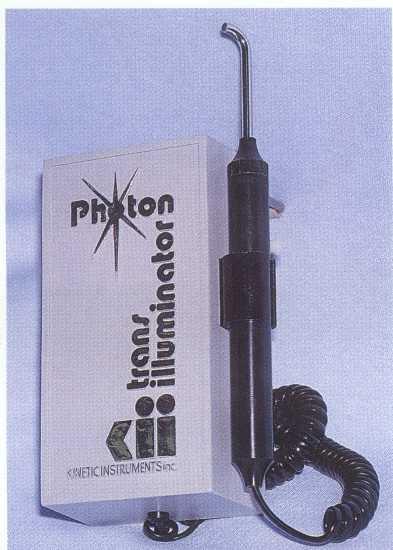

TRANSILLUMINATION/DYE STAINING. The use of a fiberoptic light (Figure 1-15) is an excellent method o£ examining teeth for coronal cracks and vertical root fractures.24 The tooth or root should be examined in the presence of minimal background lighting. The fiberoptic light is then placed on the varied surfaces of the coronal tooth structure or on the root after flap reflection. Fracture lines can be visually detected when light fails to traverse the fracture line. The fractured segment near the light appears brighter than the segment away from the light.

FIGURE 1-15 Transillumination is employed to evaluate teeth for fracture lines.